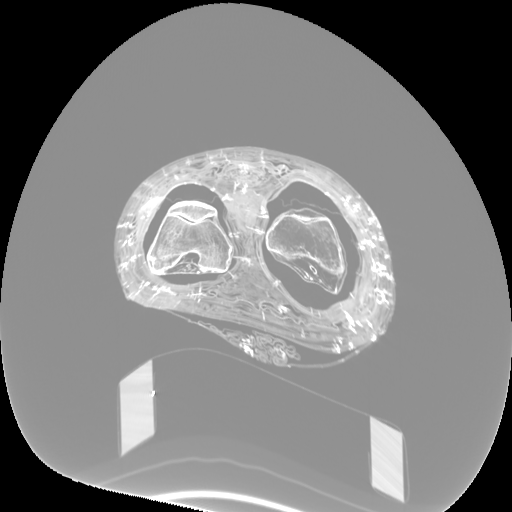

Figure 3: Visualization of axial frames of a mummy [6] selected in proximity of the thigh. (a) Some of the regions we are interested to segment are indicated. (b) Artifacts caused by presence of metals.

In Fig. 3a, we show one axial slice of a male mummy with indication of the regions to be segmented. Fig. 3b illustrates that metals present inside a bandaged mummy generate severe artifacts, which are not present in standard biomedical data.